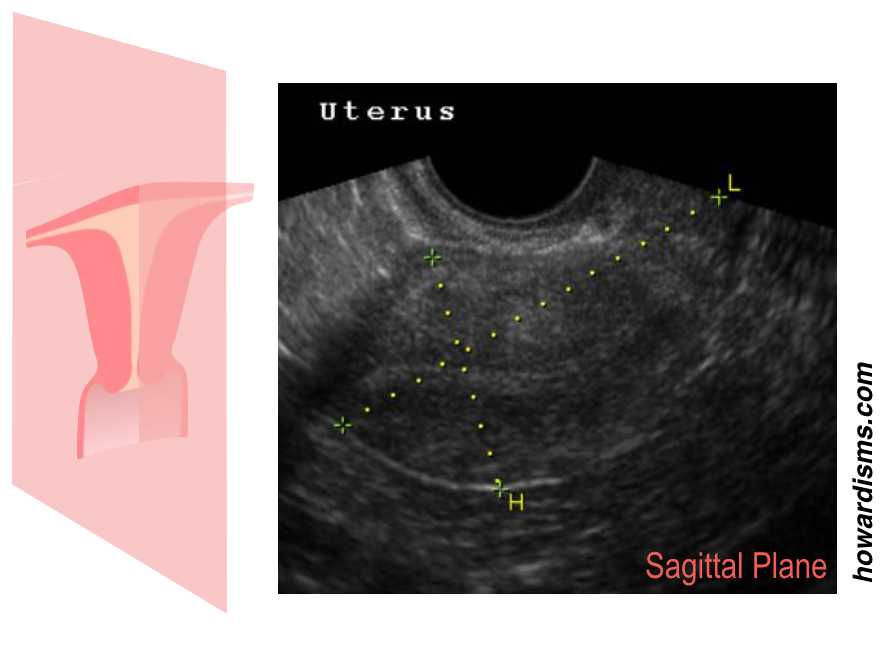

One of the most common reasons for an HSG today is to check for tubal patency. Office-based saline-infusion sonography (SIS), especially when combined with a 3D reconstruction, is very effective for providing views of the uterus and cavity and this study (so-called virtual hysteroscopy) has essentially replaced HSG for exploring uterine malformations, Asherman Syndrome, etc.